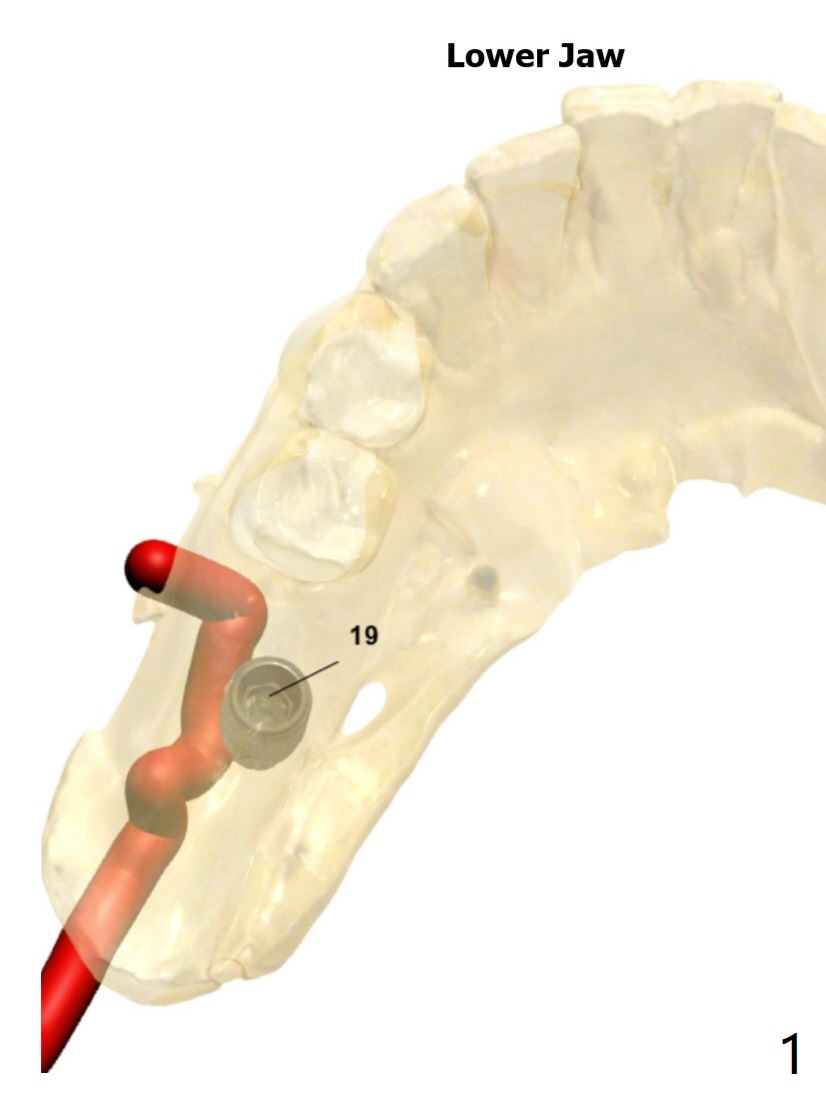

Lingual Placement  (M)

Return to Lower Molar Immediate Implant No Deviation